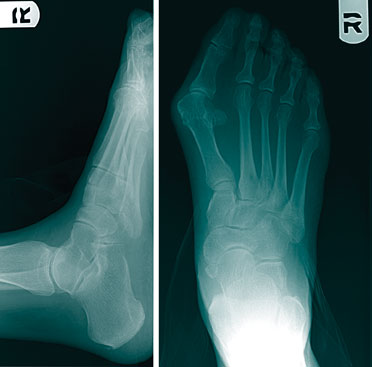

The revision bunionectomies that we have seen and performed address the undercorrection of a wide intermetatarsal (IM) angle, correction of hallux abductus and repairing a dorsiflexed capital fragment.

Nonunion of the Lapidus arthrodesis is popular to talk about but the main complication we have seen is dorsiflexion of the first ray. Other complications may include an undercorrected intermetatarsal (IM) angle and shortening of the first ray. In regard to the Lapidus procedure, while one is placing the temporary fixation, be sure to plantarflex and abduct (with laterally directed pressure) the first metatarsal.

As surgeons become comfortable with bunion surgery, we often begin to take shortcuts. For example, some may not use intraoperative fluoroscopy. It is an easy adjunctive part of a bunionectomy that only takes a couple of minutes. It can show you things you cannot always adequately visualize.These things include the position of the sesamoids, any shortening of the first metatarsal, and both the length and position of the screws.